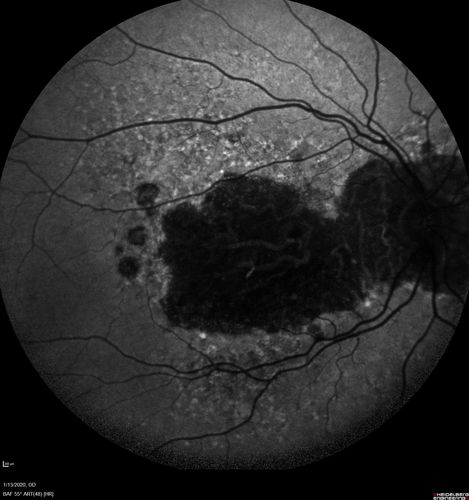

Severe Geographic Atrophy from Dry Age-Related Macular Degeneration

90 year old female with severe vision loss over the last few years.

VA 3/200 OD

1/200 OS

Geographic Atrophy from Age-related macular degeneration - Large areas